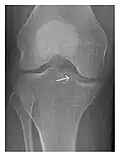

Figure 1: A 56-year-old woman presenting with left knee pain after a fall. (a) Initial anteroposterior radiograph was considered normal, however, subtle cortical disruption of the anterior rim of the medial tibial plateau, medial to the tibial spine, is noted (arrow). (b) Coronal T1-weighted MRI confirms the cortical disruption (arrow) and shows extensive fracture through the proximal tibia. (c) Coronal proton density-weighted image with fat saturation shows extensive edema in the subchondral bone. Note also hypersignal adjacent to the medial collateral ligament corresponding to a grade I sprain (arrowheads).[1]

Occult osseous injuries may result from a direct blow to the bone by compressive forces of adjacent bones against one another or by traction forces during an avulsion injury. Lesions in the tibial plateau, hip, ankle, and wrist are often missed. In a tibial plateau fracture, any disruption of the posterior and anterior cortical rims of the plateau should be sought. Impaction of subchondral bone will appear as an increased sclerosis of the subchondral bone (Figure 1). In the hip, posterior acetabular fractures also present subtle radiographic findings. The acetabular lines should then be carefully examined keeping in mind that the posterior rim, which is harder to see on X-rays, is more frequently fractured than the anterior rim (Figure 2). In the wrist, detection of carpal bone fractures is often challenging, with up to 18% of scaphoid fractures radiographically occult. Carpal fractures, especially the scaphoid, are associated with the risk of avascular necrosis. In apparently normal wrist radiographs from symptomatic patients, if there is history of a fall on an outstretched hand with pain in the anatomic snuffbox, suggesting scaphoid injury, the initial examination with posteroanterior, lateral, and pronation oblique views must be complemented by other specific views such as supination oblique and the "scaphoid" view A careful examination of cortices for evidence of discontinuity or offset and cancellous bone for lucency is necessary (Figure 3).[1]